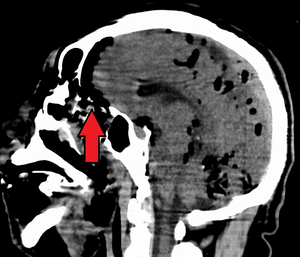

| Pneumocephalus and comminuted fracture of the frontal sinus | |

Pneumocephalus is the presence of air or gas within the cranial cavity. It is usually associated with disruption of the skull: after head and facial trauma, tumors of the skull base, after neurosurgery or otorhinolaryngology, and rarely, spontaneously. Pneumocephalus can occur in scuba diving, but is very rare in this context.